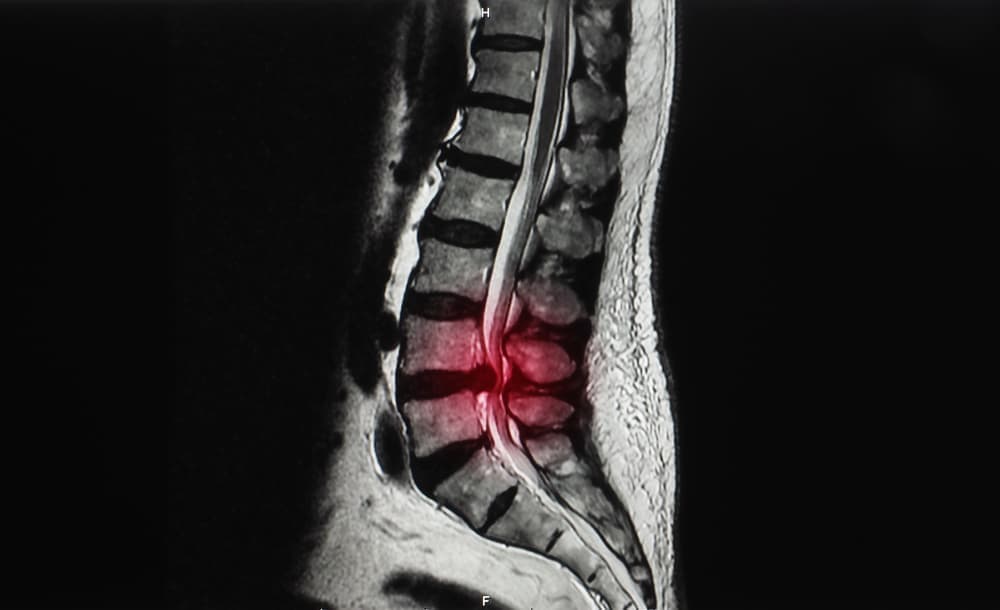

体を支える脊柱(背骨)は、一つ一つの椎骨が32個から34個連結してできています。

その椎骨の中の空洞があり、脊柱管という脊髄・血管が走る通路があります。

その脊柱管がなんらかの原因で間隔が狭まり、神経を圧迫し、痛みやしびれといった症状を及ぼすのが脊柱管狭窄症です。